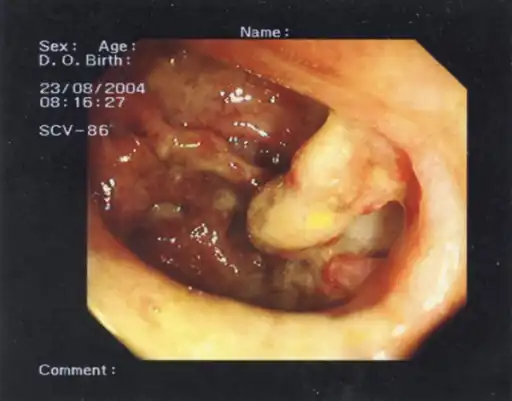

Toxic megacolon (and an appendiceal-sigmoid fistula).